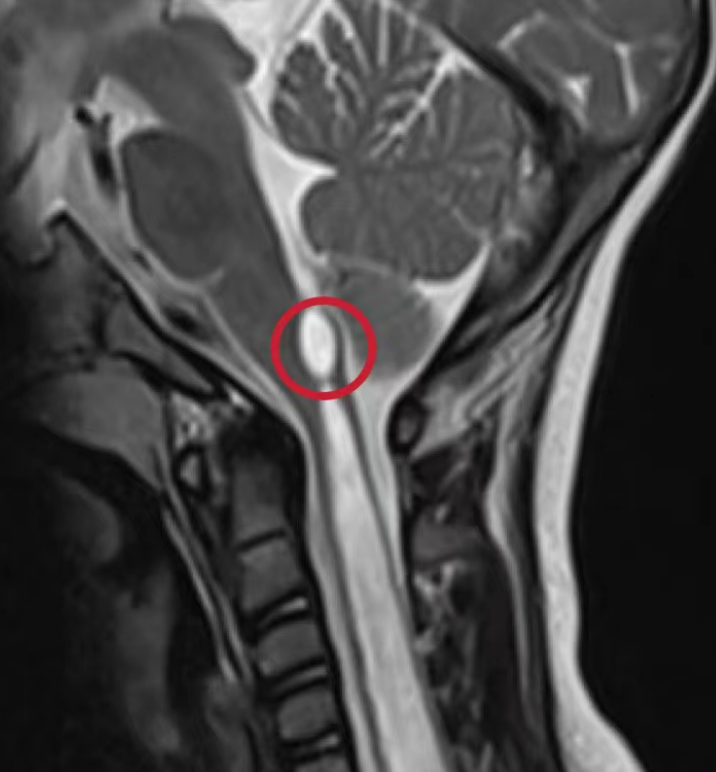

菲菲的父母带着厚厚的核磁片子马不停蹄的找到了娄永利。娄永利耐心听取了他们的疑惑和担心,并完善了脑脊液电影成像和腰椎平扫,告诉他们菲菲的脊髓空洞是由于一种少见的先天性疾病引起——脊髓栓系综合征,并非由囊变引起。

娄永利根据菲菲的情况制定了适合她的手术方案,并给出后续的治疗和康复措施。菲菲的父母听后,决定为孩子进行微创的终丝松解术,手术切口仅1.5cm。仅仅在术后第5天,再次对比同一节段的空洞已经从9.3毫米缩小至4.3毫米,短短的5毫米让菲菲的左手再一次明显感受到了这个世界的冷暖,她终于和其他孩子一样了。